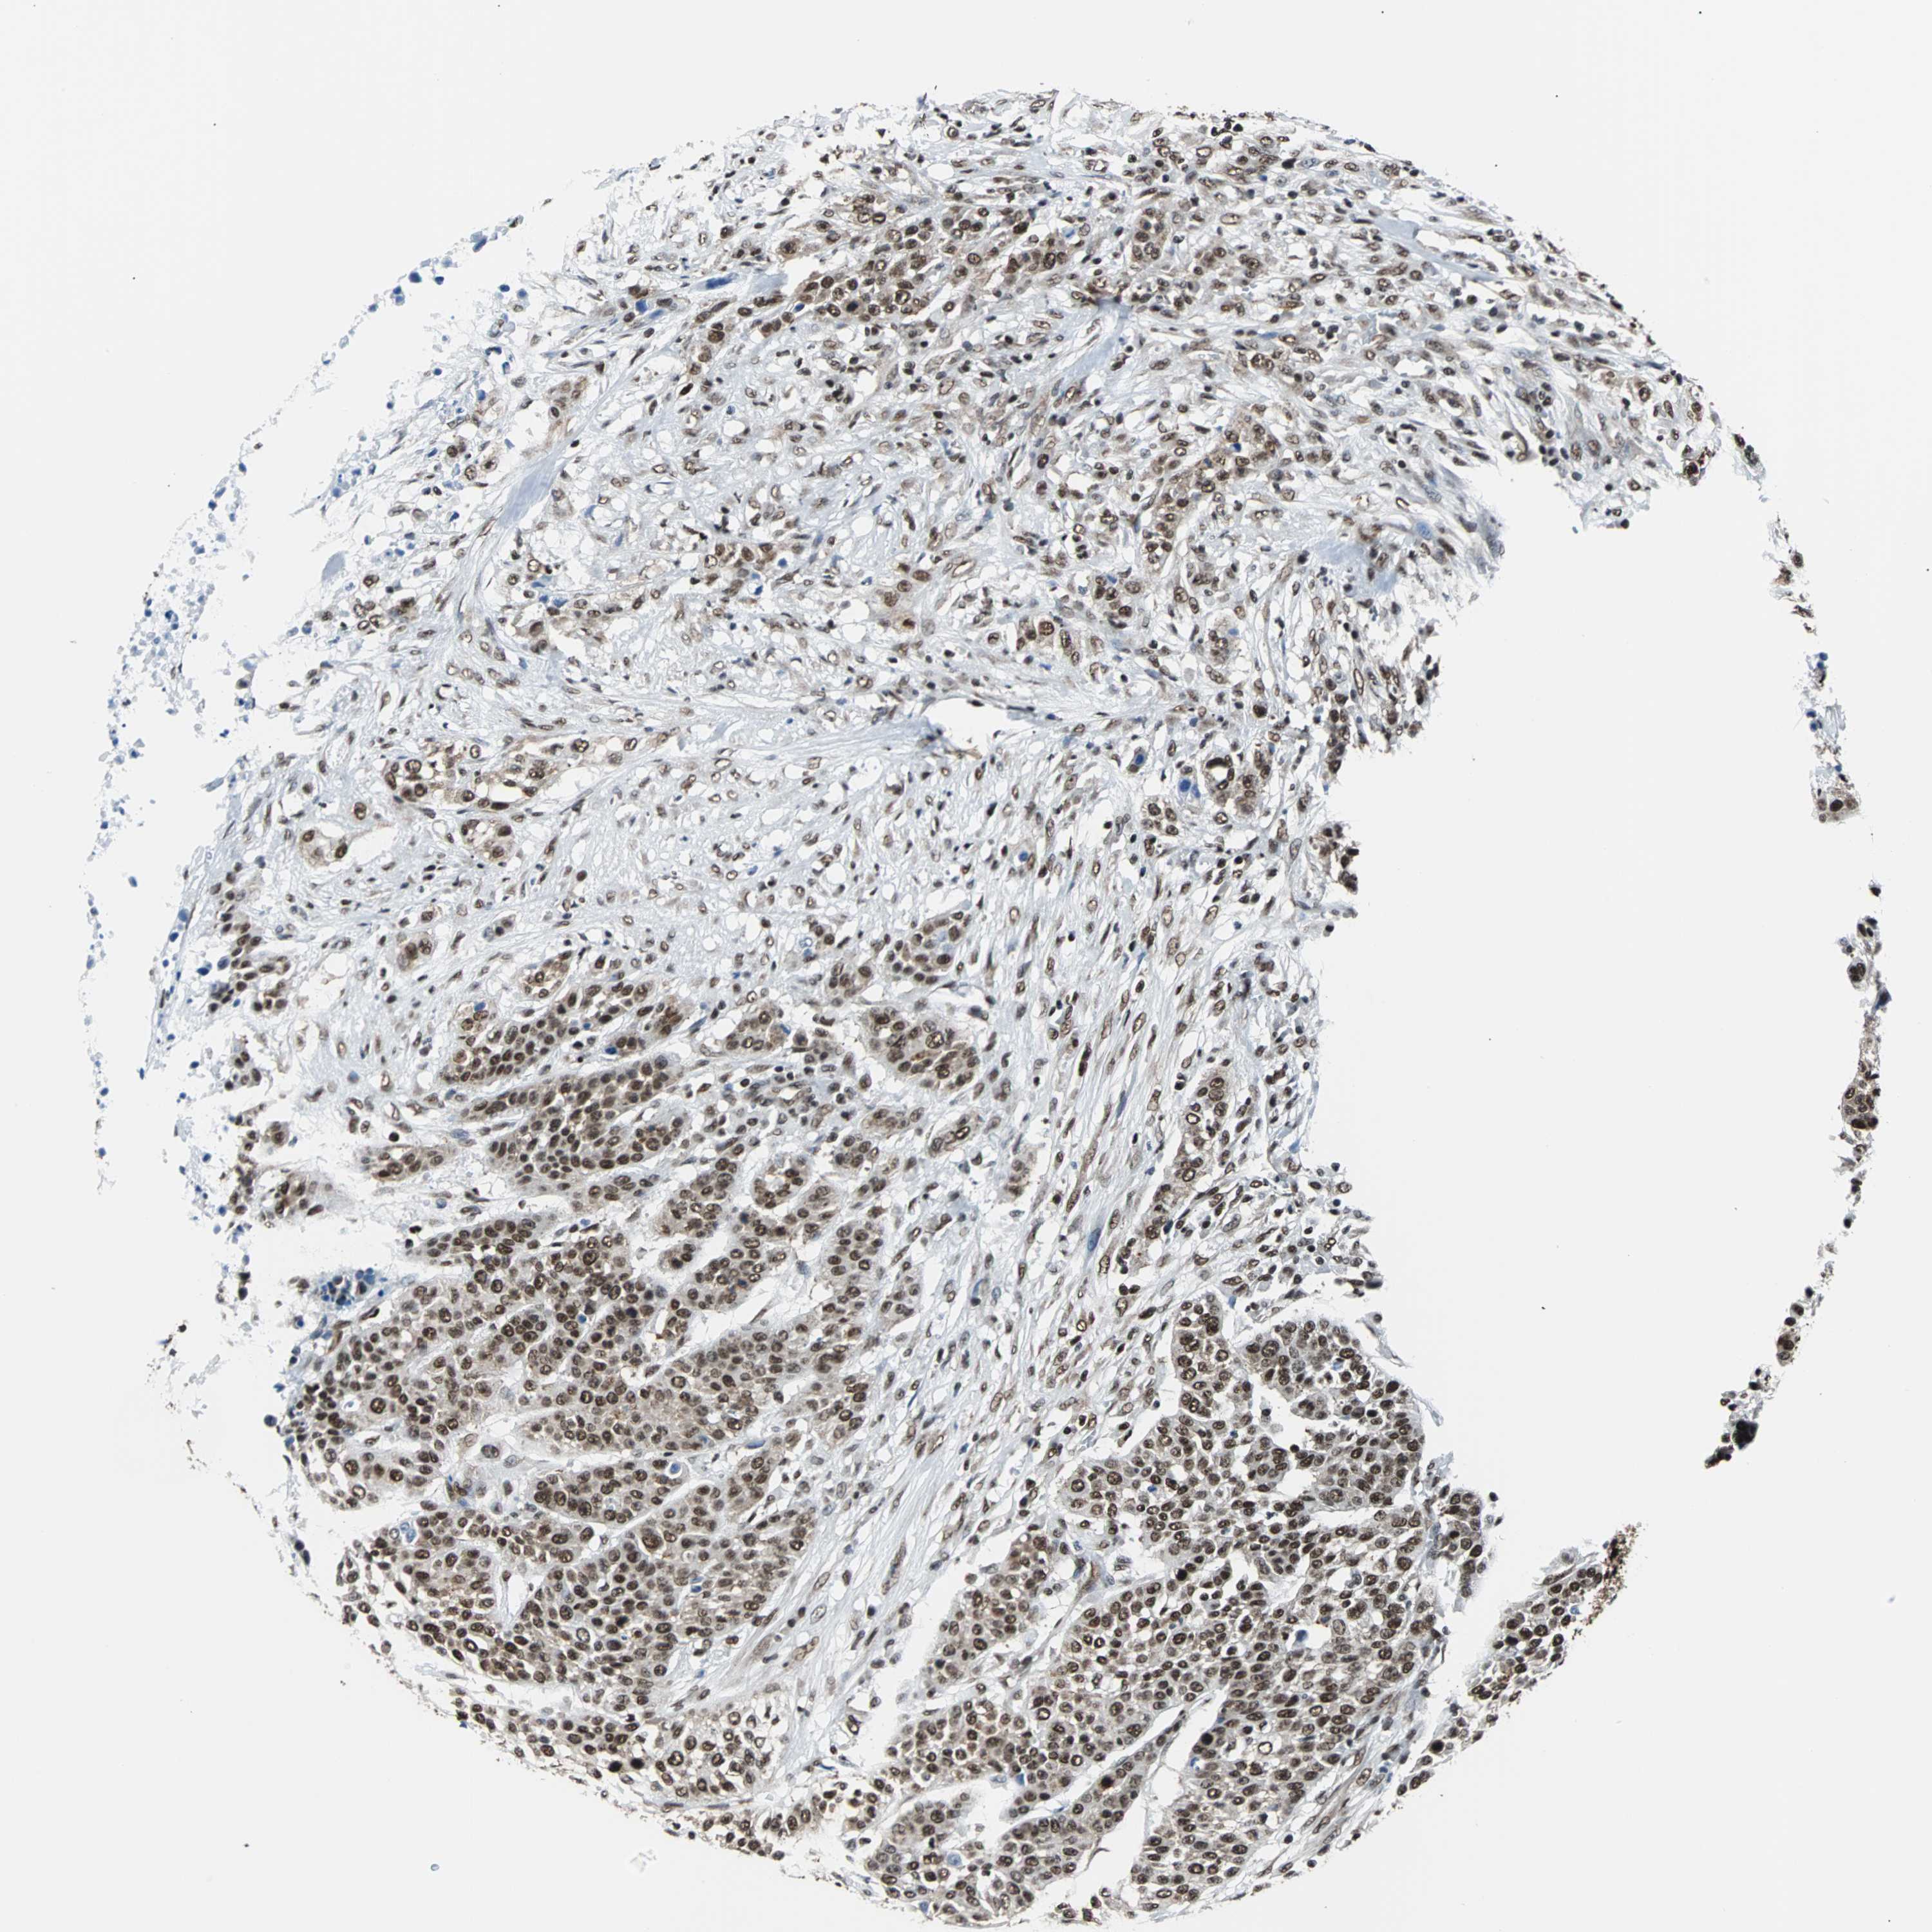

UROTHELIAL CANCER - Protein expressioni

A mouse-over function shows sample information and annotation data. Click on an image to view it in a full screen mode. Samples can be filtered based on level of antibody staining by selecting one or several of the following categories: high, medium, low and not detected. The assay and annotation is described here.

Note that samples used for immunohistochemistry by the Human Protein Atlas do not correspond to samples in the TCGA dataset.

Antibody stainingi

Antibody staining in the annotated cell types in the current human tissue is reported as not detected, low, medium, or high, based on conventional immunohistochemistry profiling in selected tissues. This score is based on the combination of the staining intensity and fraction of stained cells.

Each image is clickable and will lead to virtual microscopy that enables deeper exploration of all samples and also displays staining intensity scores, fraction scores and subcellular localization as well as patient and tissue information for each sample.

Antibody HPA006149

Staining

High

Medium

Low

Not detected

Intensity

Strong

Moderate

Weak

Negative

Quantity

>75%

75%-25%

<25%

None

Location

Nuclear

Cytoplasmic/membranous

Cytoplasmic/membranous,nuclear

Urothelial carcinoma, High grade

Urothelial carcinoma, Low grade